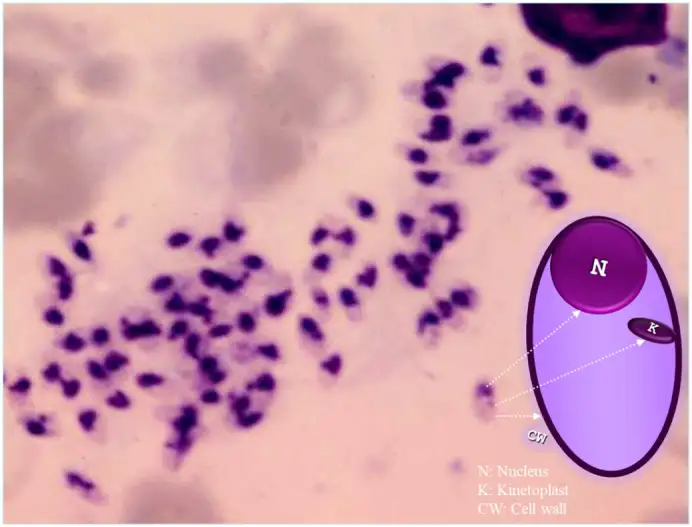

一九〇三年五月,一位名叫威廉·利什曼的英国军医在伦敦的皇家陆军医学院报告了一项重要发现。他在一名死于"黑热病"的印度士兵的脾脏中发现了大量微小的寄生生物。利什曼描述这些生物为"椭圆形小体",每个都包含两个深染的结构——一个是细胞核,另一个是一个特殊的细胞器,后来被称为动基体。他推测这是一种新的寄生虫,但当时无法确定它的分类地位。

同一年,在印度马德拉斯工作的爱尔兰医生查尔斯·多诺万也在黑热病患者的脾脏穿刺标本中观察到了同样的寄生虫。多诺万进一步证明,这些寄生虫可以通过脾脏穿刺从活体患者中获得,这为临床诊断开辟了新的途径。为了纪念这两位几乎同时发现的科学家,人们将黑热病脾脏中发现的寄生虫形态命名为"利什曼-多诺万小体"。

利什曼原虫的无鞭毛体是椭圆形的寄生虫,长约二到四微米,具有一个偏心的细胞核和副核动基体。它们可以在巨噬细胞的细胞质内或细胞外被发现,常常呈现出"蜂群"样的排列。这是诊断利什曼病的关键形态学特征。